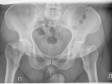

коксартроз

данила

Больше всего беспокоит: редкие боли в колене и в паховой области при нагрузке

Прикреплённые файлы: